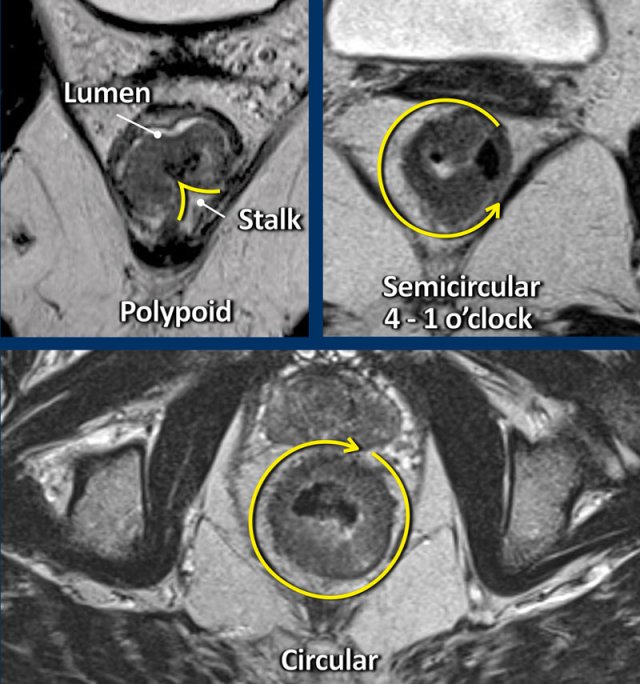

Polypoid and Sessile tumors

Rectal adenocarcinomas typically arise from adenomas that can be either polypoid, which are tumors raised upon a stalk or sessile, which are flat.

Polypoid tumors generally represent more low-grade malignancies and present as a mass projecting into the bowel lumen with a focal attachment or stalk to the bowel wall.

Sessile tumors typically present as a semi-circular or circular wall thickening.

The site where the tumor is attached to the rectal wall is often referred to as the “invasive margin” and is the site where we need to focus on when assessing the T-stage and looking for extramural tumor extension.

The degree of attachment to the rectal wall, also referred to as the tumor circumference, can be described in the radiology report as “from … to … o’clock”, or alternatively using prose descriptions such as “left anterolateral”.